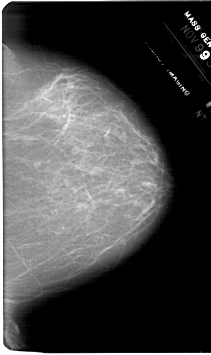

A_1768_1.LEFT_CC

LEFT_CC LINES 6871 PIXELS_PER_LINE 4231 BITS_PER_PIXEL 12 RESOLUTION 43.5 OVERLAY

FILE: A_1768_1.LEFT_CC.OVERLAY

TOTAL_ABNORMALITIES 1

ABNORMALITY 1

LESION_TYPE MASS SHAPE OVAL MARGINS OBSCURED

ASSESSMENT 4

SUBTLETY 2

PATHOLOGY BENIGN

TOTAL_OUTLINES 1

BOUNDARY